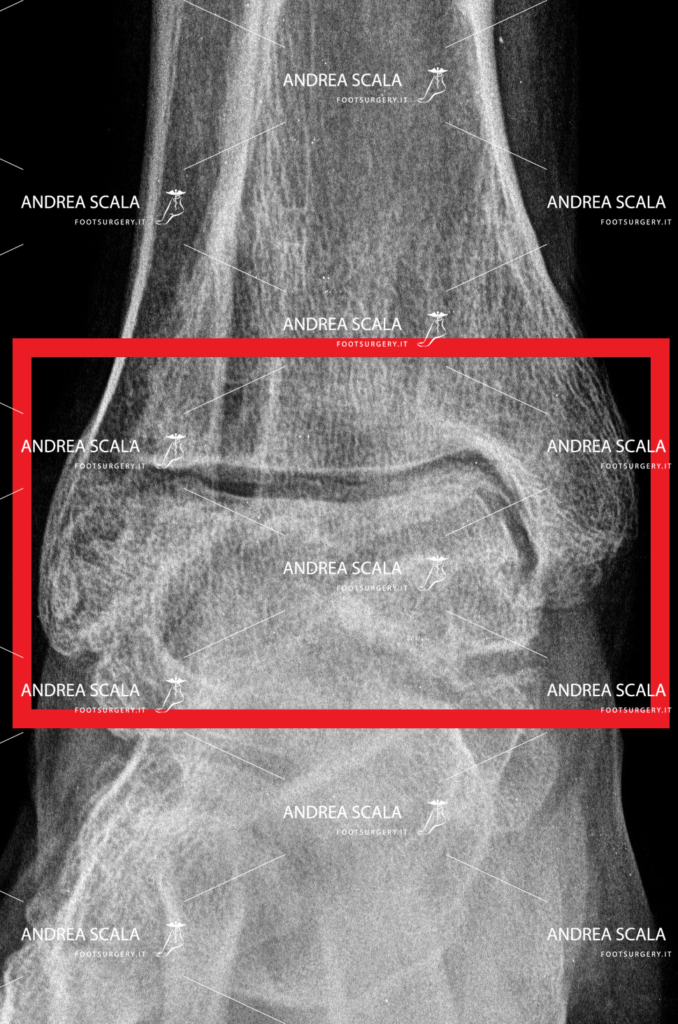

Come si diagnostica l’artrosi alla caviglia?

Con un’analisi attenta dei sintomi, alla quale va immediatamente accompagnata una radiografia che ha lo scopo di far emergere le evidenze più marcate legate all’artrosi, ovvero una rima articolare assottigliata, il rimodellamento dell’osso che si trova al di sotto della cartilagine articolare, la presenza di cisti ossee e piccoli speroni ossei.